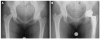

Osteonecrosis is a phenomenon involving disruption to the vascular supply to the femoral head, resulting in articular surface collapse and eventual osteoarthritis. Although alcoholism, steroid use, and hip trauma remain the most common causes, several other etiologies for osteonecrosis have been identified. Basic science research utilizing animal models and stem cell applications continue to further elucidate the pathophysiology of osteonecrosis and promise novel treatment options in the future. Clinical studies evaluating modern joint-sparing procedures have demonstrated significant improvements in outcomes, but hip arthroplasty is still the most common procedure performed in these affected younger adults. Further advances in joint-preserving procedures are required and will be widely studied in the coming decade.